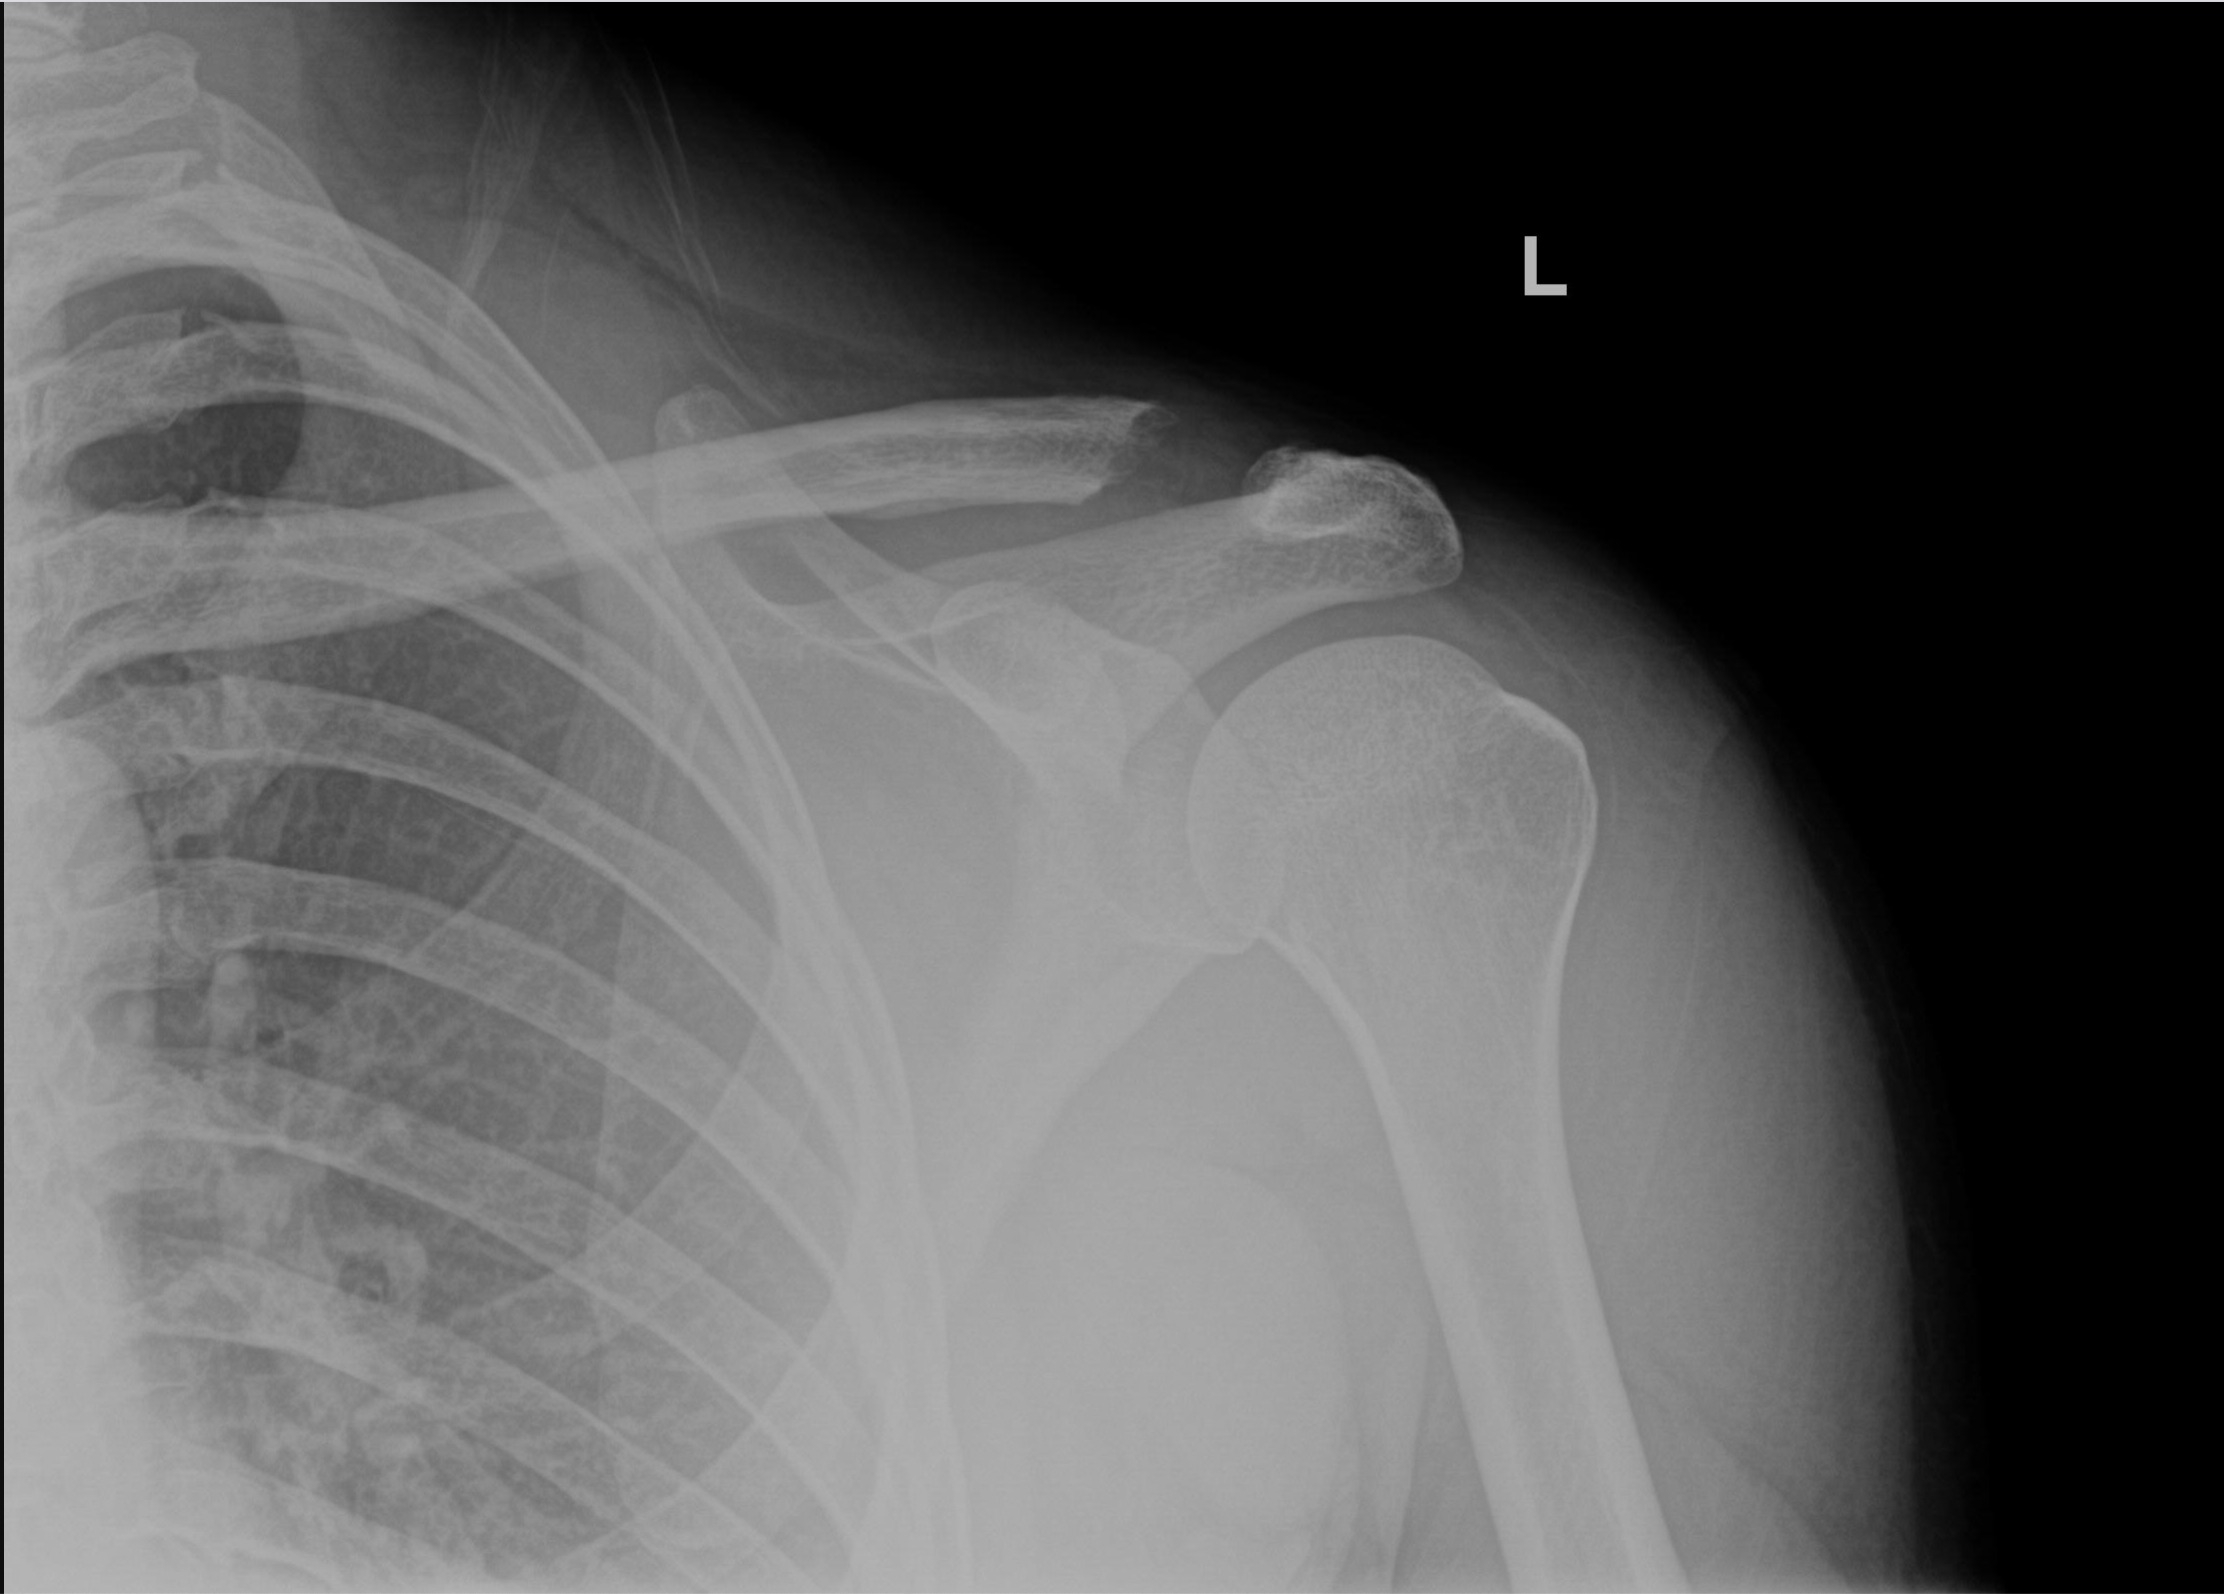

Broken clavicle, before and after my surgery r/XRayPorn When Can I Shower After Clavicle Surgery In general, you can shower 24 hours after. The arm can hang gently at the patient's side while showering. Healing of the fracture may take 3 to 5 months. These should be left in place until removed in clinic. Arm in a sling for comfort. Most clavicle fractures heal after about 6 to 12 weeks. Do not submerge the wounds. When Can I Shower After Clavicle Surgery.